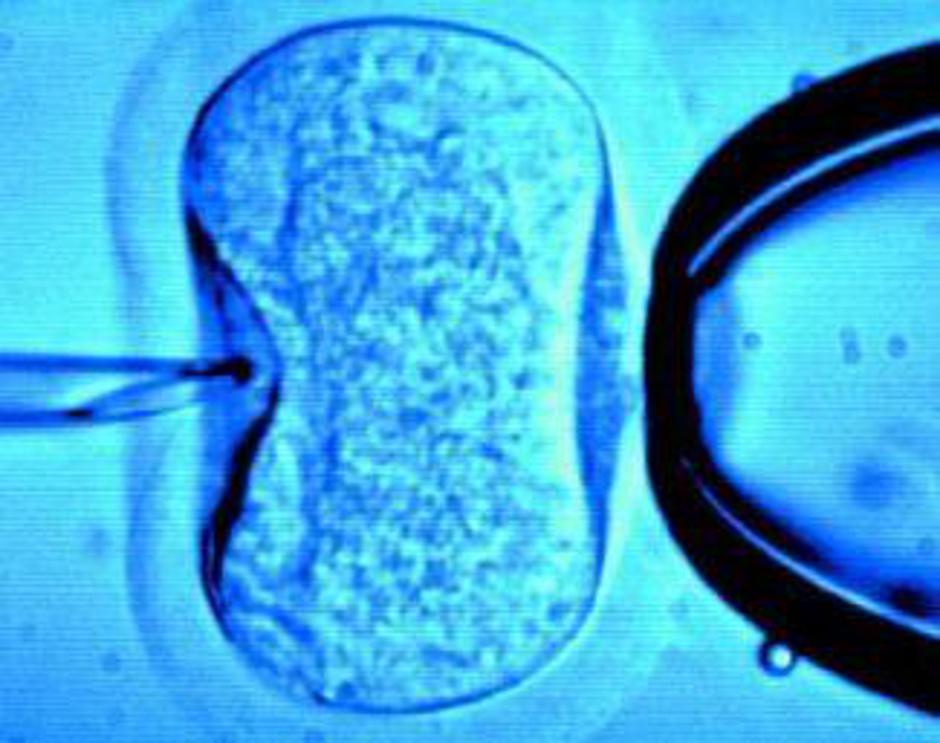

Oploditev z biomedicinsko pomočjo

Po novem se bo število omejitev oploditev z biomedicinsko pomočjo nanašalo le na zunajtelesno oploditev. V novih pravilih pojasnjujejo, da do sedaj določba ni odražala dejanskega izvajanja te pravice. Po veljavni medicinski doktrini se namreč najprej izvedejo postopki znotrajtelesne oploditve, če ti niso uspešni, pa se izvedejo postopki zunajtelesne oploditve, ki pa so omejeni po številu. Namesto izraza "ciklus", ki v veljavnih predpisih ni posebej opredeljen, se zaradi večje jasnosti uporablja izraz "postopek."

Sicer so ti postopki še vedno omejeni glede na starost ženske; pravico do biomedicinske pomoči  imajo ženske od dopolnjenega 18. leta starosti do dopolnjenega 43. leta starosti. "Enako kot do sedaj se pri ženski, mlajši od 35 let, pri prvih dveh postopkih zunajtelesne oploditve opravi elektivni prenos enega zarodka dobre kakovosti. Prav tako še naprej velja, da se postopek oploditve z odmrznjenimi zarodki šteje v tisti postopek, v katerem so bili zarodki zamrznjeni."